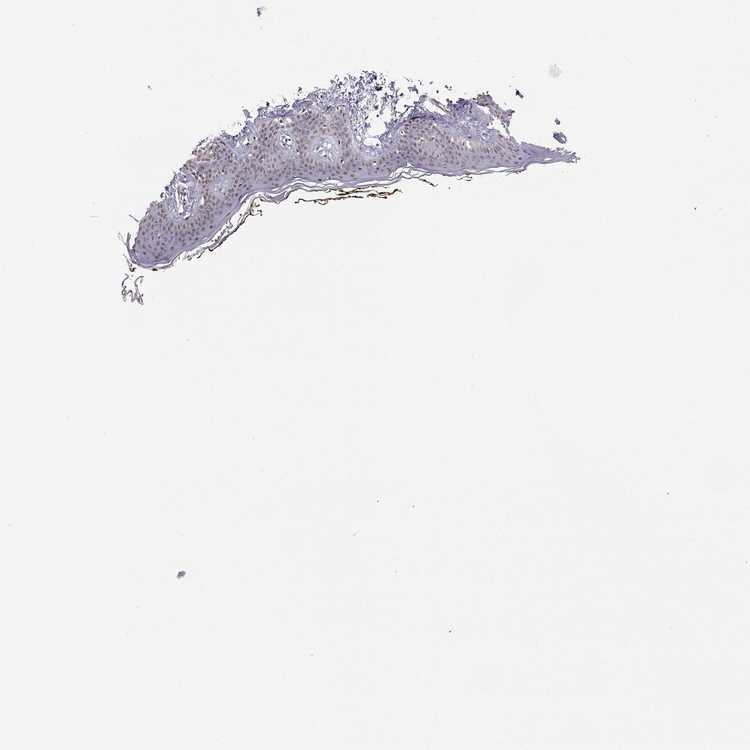

SKIN 1 - Antibody stainingi

Antibody staining in the annotated cell types in the current human tissue is reported as not detected, low, medium, or high, based on conventional immunohistochemistry profiling in selected tissues. This score is based on the combination of the staining intensity and fraction of stained cells.

Each image is clickable and will lead to virtual microscopy that enables deeper exploration of all samples and also displays staining intensity scores, fraction scores and subcellular localization as well as patient and tissue information for each sample.

Antibody HPA077684

Langerhans Medium

Fibroblasts Not detected

Keratinocytes Medium

Melanocytes Low

SKIN 2 - Antibody stainingi

Epidermal cells Medium